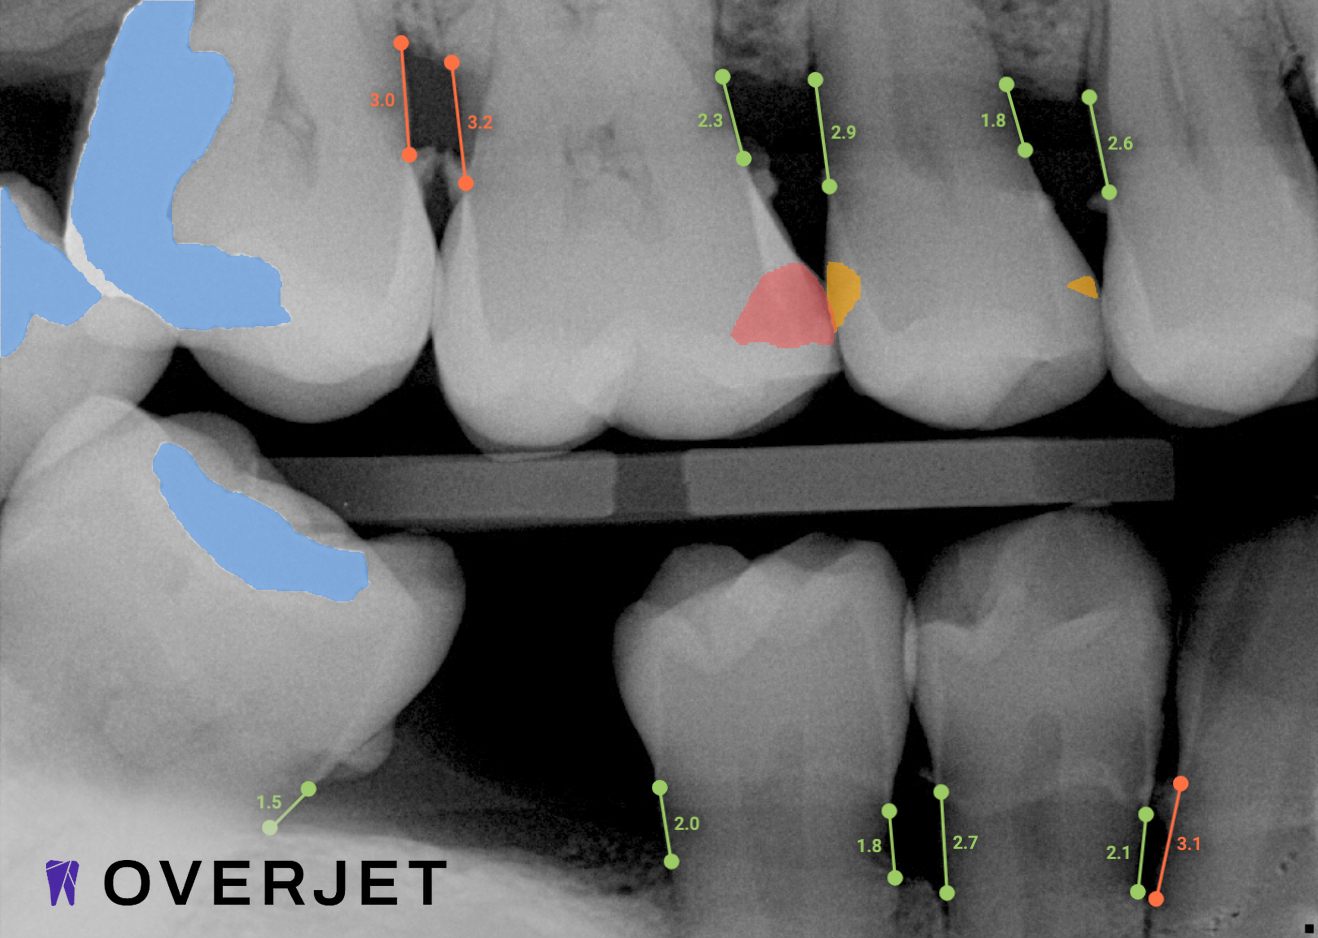

See More with AI

Where Advanced Technology Meets Personalized Care

Overjet AI's patient-centric technology combines human intelligence with the power of artificial intelligence.

Best in class dental care for every patient, on every visit.

Confidence in Your Diagnosis

Our practice is proud to provide the best technology in the dental industry, including Overjet AI for instant X-ray analysis.

Overjet’s artificial intelligence technology transforms traditional black-and-white X-rays by adding a layer of data that instantly outlines decay (cavities) and measures bone loss. This makes it easy for you to see your results alongside your dentist. It’s like getting a second opinion delivered instantly. With Overjet’s analysis and easy-to-read presentation, you will have the information you need to make an informed decision about your oral health. Together, we’ll review your findings and discuss the best steps to take to achieve your goals.